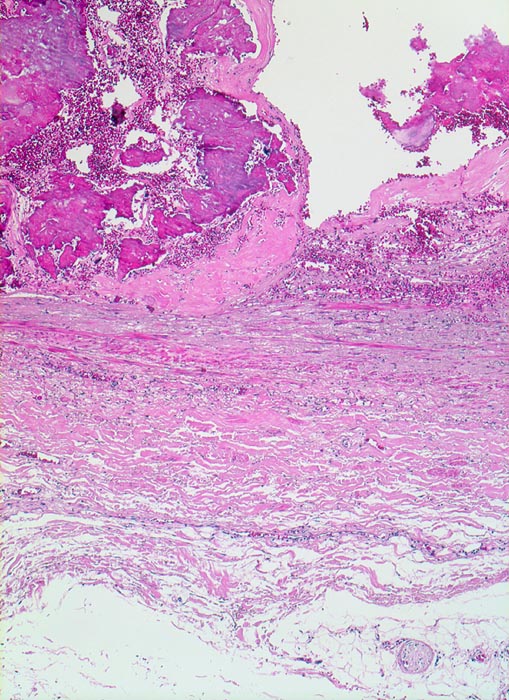

Atherosklerose

vaskulär / Durchblutungsstörung

Arteria poplitea

Die sklerosierte Intima enthält grobschollige bläuliche Verkalkungen mit frischen Einblutungen. Die Muskelschicht der Media ist atroph.

Patient mit arterieller Hypertonie und 42 Pack Years Nikotinabusus. Klinisch PAVK IIa mit gelegentlichen leichten Schmerzen im rechten Bein nach längeren Gehstrecken.